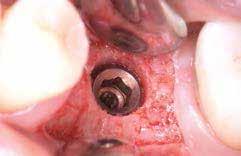

A 2.5-ös fog mentén periotómot haszáltunk, hogy átvágjuk a periodontális rostokat, így a fogat kilazítottuk, hogy ezzel is csökkenthessük a fogó által végzendő laterális mozgások szükségességét, illetve hogy a környező csontot is a legnagyobb mértékben megőrizzük. Nem volt elég csont (anélkül, hogy perforálnánk az arcüreg alapját) ahhoz, hogy abban stabilizáljuk az implantátumot, úgy döntöttünk, hogy behelyezünk egy ∅ 5.0 x 12 mm-es Straumann® BLX implantátumot közvetlenül az alveolusba, előfúrás nélkül. Az implantátum menetkialakítása lehetővé tette, hogy a kézidarabbal behajtva, 25 Ncm-es nyomatékot érjünk el, majd racsnis nyomatékkulcs segítségével juttattuk a végső pozíciójába, 80 Ncm-es behajtási nyomatékot mérve (3. és 4. ábrák).

A 2.6-os fog helyén egy 6 mm mély furatot készítettünk a gyártó előírása szerint, a puha csont protokoll lépéseit követve. Egy ∅ 5.0 mm × 6 mm Straumann® BLX implantátumot helyeztünk be 50 Ncm-es behajtási nyomatékkal (5. ábra)

A 2.7-es fog helyénél egy disztális irányú, 14 mm mély, ferde előfúrást végeztünk, elkerülve a sinus maxillarist a tuber csontkínálatának felhasználásával. Egy ∅ 5.0 mm x 14 mm Straumann® BLX implantátumot helyeztünk be, 50 Ncm-es behajtási nyomatékkal (6. ábra)

Mind a három implantátumba gyógyulási csavar került, ezzel elkerültük az újabb sebészi beavatkozás szükségességét.

Tovafutó varrattal zártuk a sebet az ínyformázó csavarok körül (7. és 8. ábrák).